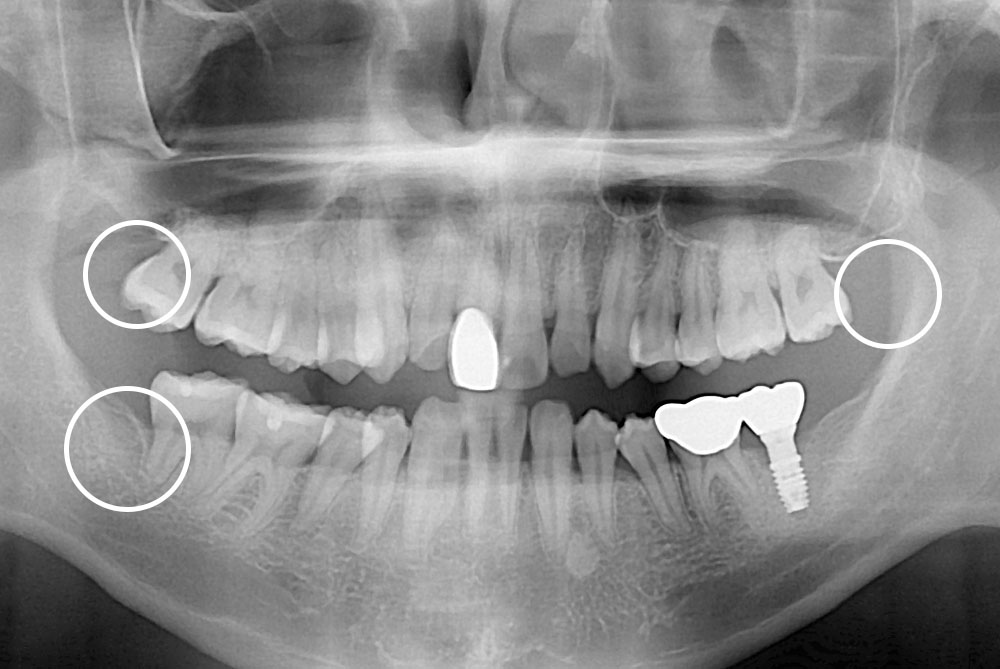

[사랑니] 매복 사랑니 발치

치료후 : 2021-10-27

세종치과는 구강악안면외과학 박사이신 원장님이 발치하는 치과입니다.